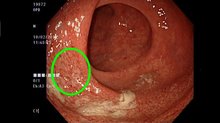

台灣發炎性腸道疾病學會翁昭旼理事長指出,發炎性腸道疾病為腸道免疫系統過度反應與錯誤識別所引起,依發炎分佈型態、侵犯腸壁程度,可分為潰瘍性結腸炎和克隆氏症,由於症狀與大腸激躁症類似,均為腹痛、腹瀉,因此常被患者所忽略。

台灣發炎性腸道疾病學會也提出5大警訊,提醒症狀若持續3個月以上,務必積極就醫,其中包括貧血、發燒、血便、腹痛,及腹瀉(裡急後重、糞便失禁等)。

治療方面,吳登強說明,以往柔腸寸斷的發炎性腸道患者因腸道組織壞死,通常只有切除一途,所幸現在第四代腸道專一生物製劑已解決這個困境,可讓淋巴球、白血球不再跑到腸道組織胡亂殘殺自體正常細胞,並有效緩解腸道發炎現象,大幅降低感染風險。此外,腸道專一生物製劑已於106年10月獲得健保給付,這讓病友多了一項治療的利器。